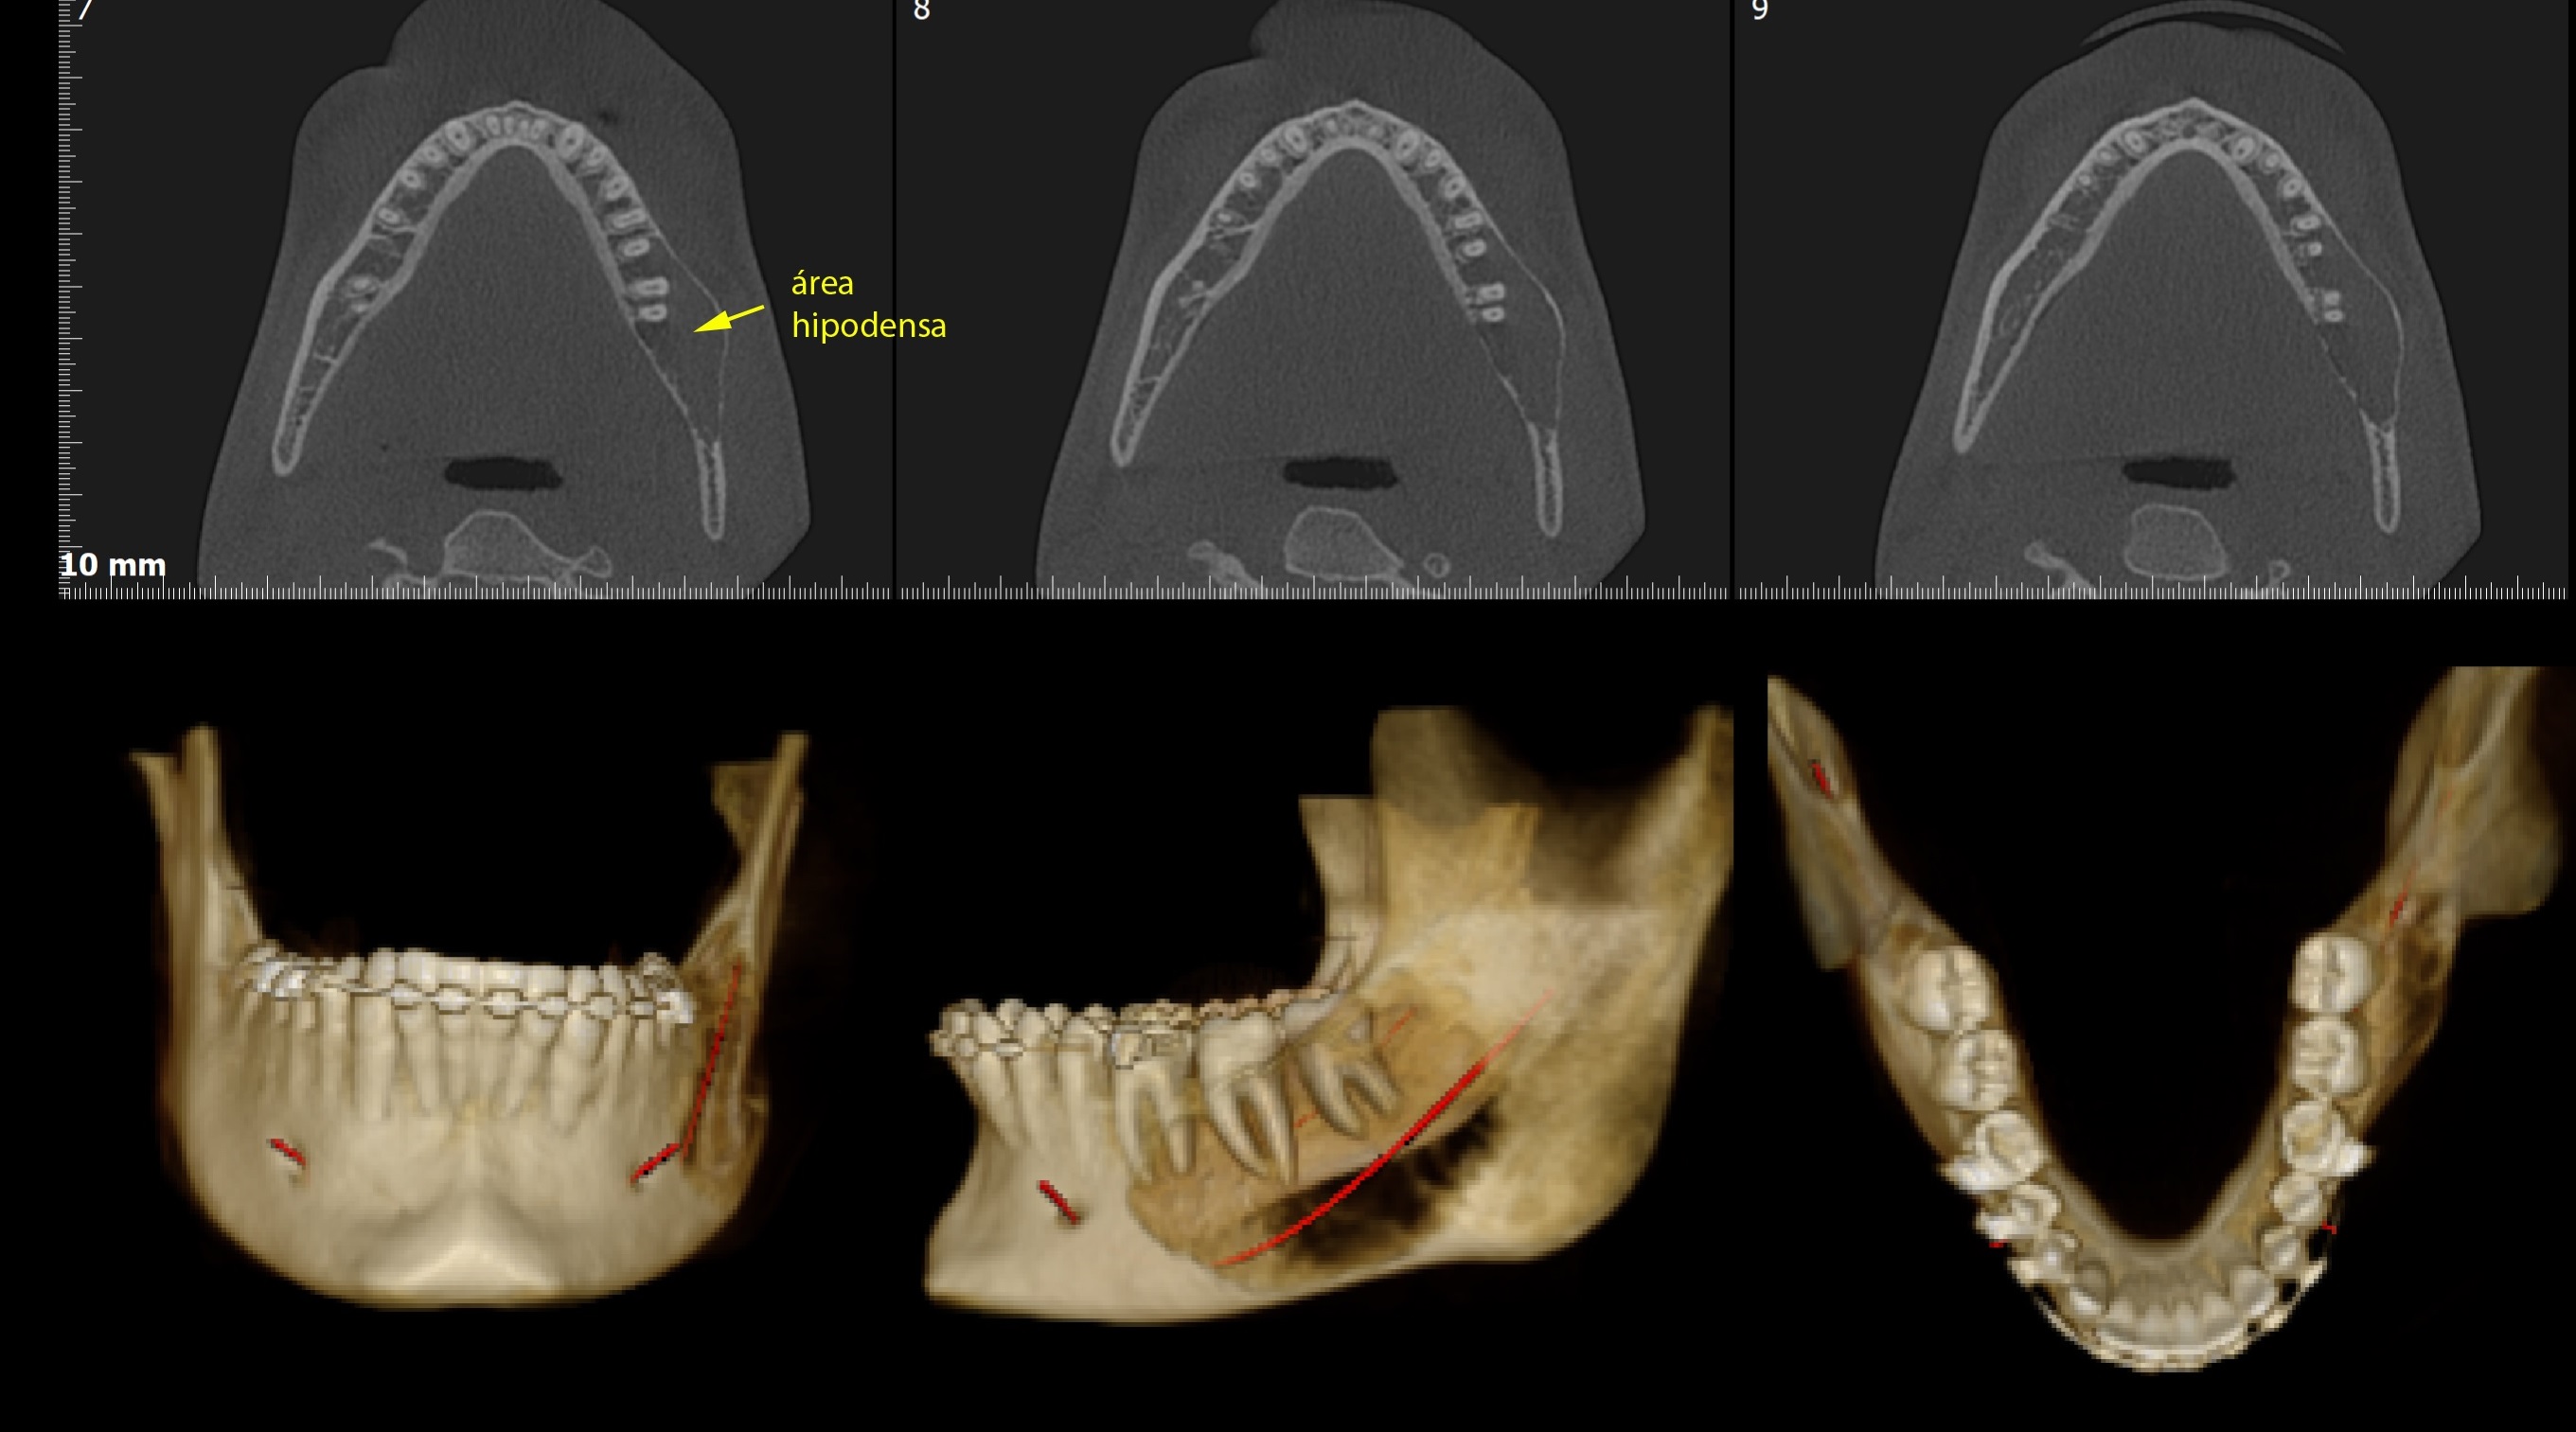

TOMOGRAFIA COMPUTADORIZADA VOLUMÉTRICA CONE BEAM

Laudos e Análises Radiográficas